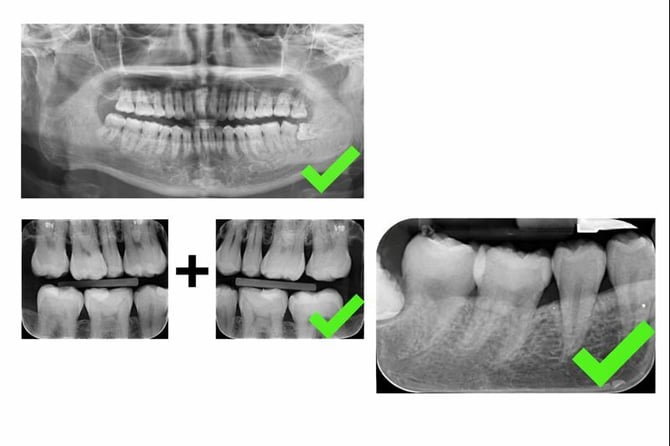

Radiographs

-

OPG (≤ 3 years)

Supports analysis of bone levels, wisdom teeth, and periapical findings -

Bitewings – left & right (≤ 2 years)

Used to assess caries and bone loss -

Periapical X-rays (≤ 2 years)

Supports periapical and bone-related observations